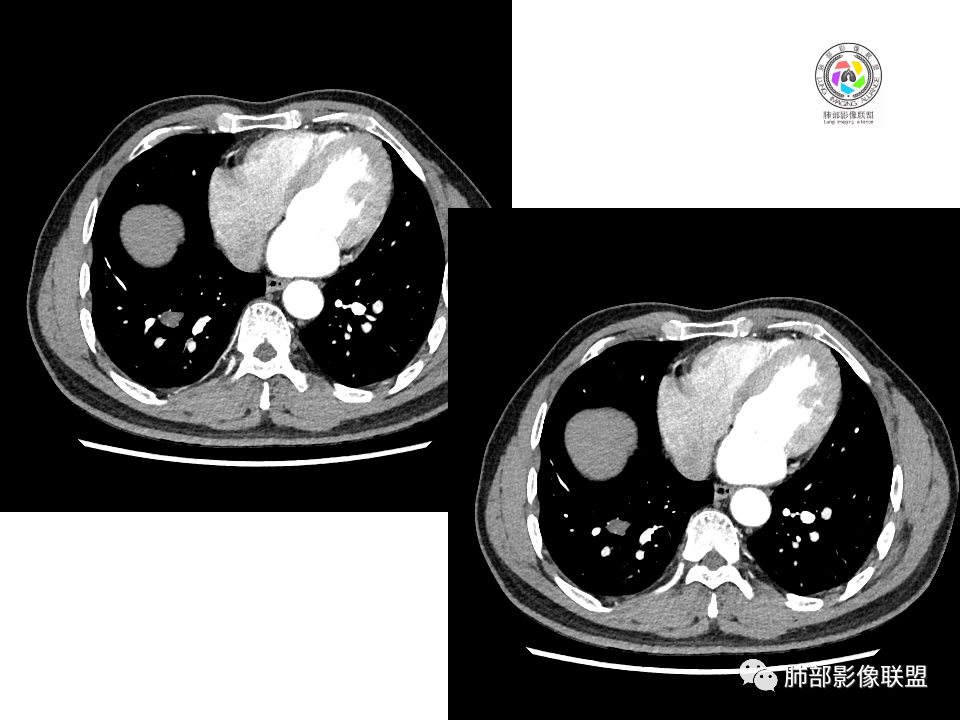

南边:这两个一元论的病灶考虑:

①炎性:隐球菌;

②恶性:间叶来源肿瘤,间叶来源的两个病灶的罕见;癌一般还是与支气管关系密切,有如果考虑癌,自然是小细胞癌(山丘征);但是因为没有看到支气管具体情况,不太踏实。

有老师分析,多发病灶有磨玻璃晕,可以符合隐球菌感染,确实如此。但背段边缘如此锐利的块影还是更容易让人联想到新生物。

1、普通人隐球菌感染的时相:初期的隐球菌感染周围有晕,晕从多变少,或包裹,或吸收,结节实性区可迅速变大。后期(慢性期)的隐球菌周围无明显晕征,边界较清楚。

3、卫星灶与“蘑菇兄弟”:诊断隐球菌时,建议找卫星灶,卫星灶可以在遥远的地方。可以是遥远地方的微小结节——“小蘑菇兄弟”。有些远处的卫星灶,通常是不规则饱满实性的,晕征不明显。隐球菌的卫星灶非常“隐”,但发现率高达60%多,诊断价值高。

5、周围毛刺纤维、边缘形态等:坏死包裹会使得结节变圆;结节多缺乏明显的分叶征,缺乏局部突出生长能力;如果出现分叶,是由多处肉芽肿中心形成。没有坏死的局限化,结节只是凑合在一起,常呈方形征;毛刺进入晕区(概念源自南边老师),毛刺较短、较软;周围的晕吸收后,会留下不规则边,外面常残留丝状条索;收缩力较弱,临近胸膜对胸膜牵拉不明显。